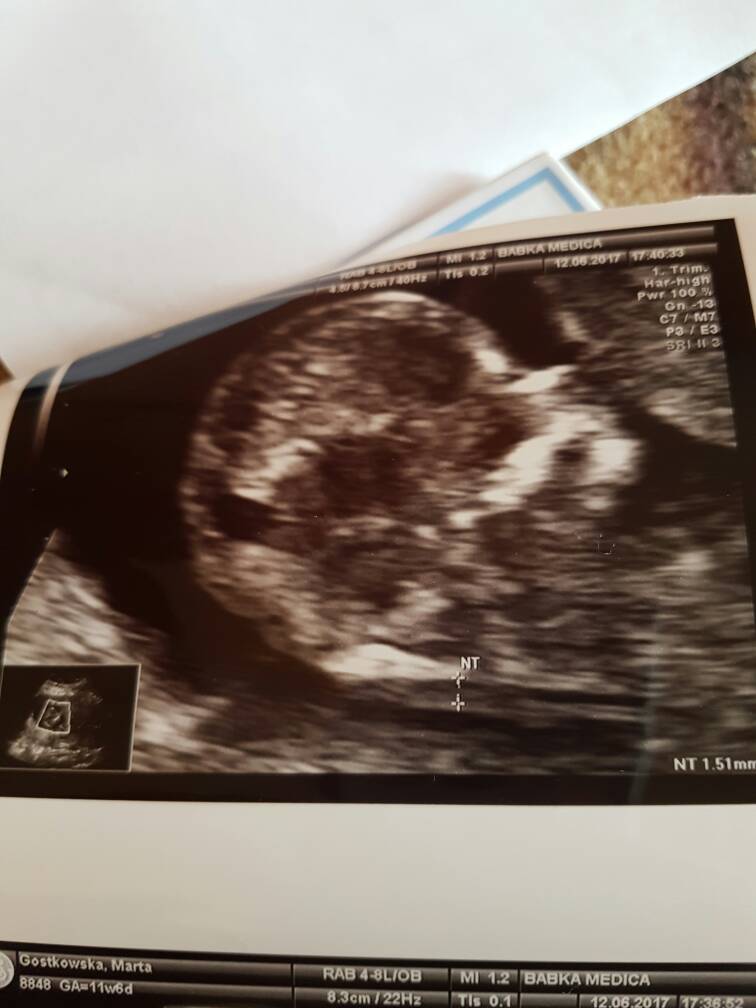

Wszystko dobrze. Dzidzius ma 12tyg6 dni według usg czyli prawie tydzień starszy niż z OM.

6,6 cm człowieka [emoji7]

Przezierność karkowa 1,51mm

Ryzyko wad bardzo niskie.

Niestety dzidzius zacisnąl nóżki i nie pokazał co tam ma.